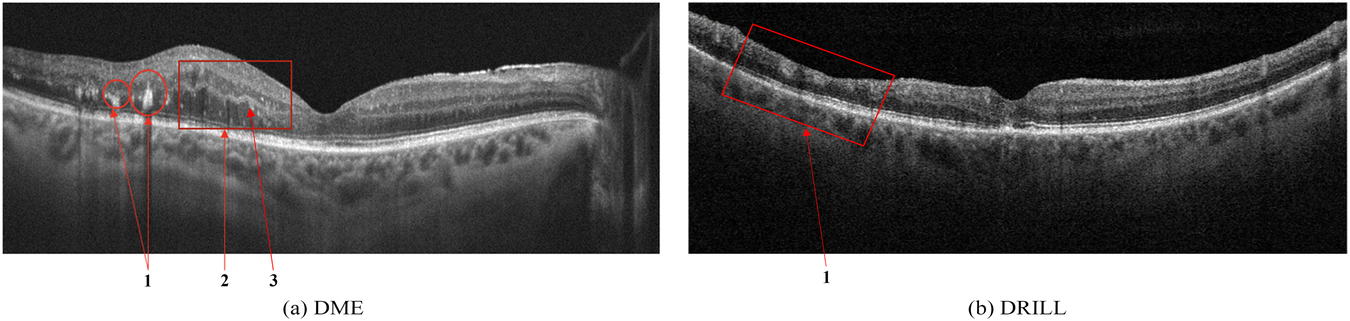

(a) Signs of Diabetic Macular Edema (DME): 1 - Hard exudates (HE), 2 - Intraretinal fluid (IRF), 3 - Hyperreflective foci; (b) Disorganization of retinal inner layers (DRIL).